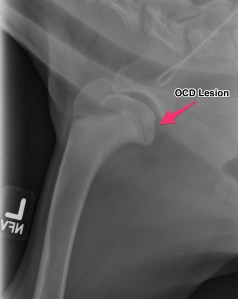

Radiographs (X-rays)

Above are x-rays of a left and right shoulder affected with OCD lesions. These are on the same patient. The images labeled with the left (L) marker has a flattened region noted by the arrow which is characteristic of OCD. The image on the right has the area highlighted in blue. While the lesion doesn’t look big, it can definitely cause a lot of pain and discomfort.